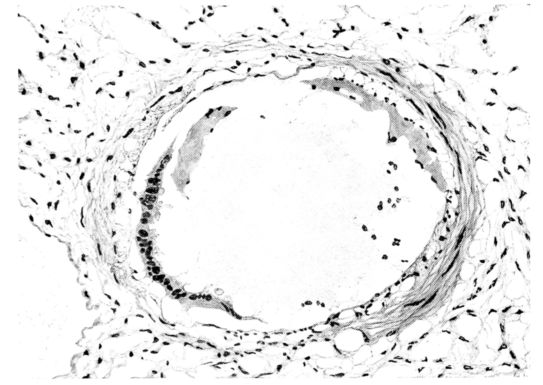

FIG. IV. AUTOPSY NO. 205. CONGESTION AND EDEMA OF THE SUBMUCOSA AND REGENERATION OF THE TRACHEAL EPITHELIUM.

The changes are less marked, perhaps, in the trachea than in its finer ramifications. The mucosa is constantly more or less destroyed and large areas, usually focal, are entirely devoid of their epithelial covering. This is replaced by a sparse exudate, composed largely of red blood cells, mucus, a small amount of fibrin, and nuclear fragments (Fig. II). It may dip into the submucosa for a short distance, but usually these indentures are associated with the ducts of the mucous glands into which the inflammatory reaction extends. A more striking feature than the exudate, however, is the edema and the congestion of the submucosa. The loose areolar tissue of the submucosa is spread widely apart, and throughout it distended blood vessels are very conspicuous. Occasionally such a vessel is broken and actual hemorrhage appears in the submucosa. Occasionally, too, the inflammation extends down the duct to the mucous gland itself, and here, also, aplastic inflammatory reaction is evident, inasmuch as the acini now stain intensely red with the cells undifferentiated from each other and specked here and there by broken remains of the dead nuclei (Fig. III). After the disease has continued for a short period, even at the end of five or six days, some regeneration of the epithelial lining may be seen (3) (Fig. IV). But despite this, the acute picture persists, and there goes on, side by side, an attempted repair characterized by epithelial regeneration and the same evidence of acute change. Since the lesion is essentially a superficial one, scars or contractures of any extent are not encountered in the trachea, even in examples of the disease that have ended fatally only after many weeks.[4]